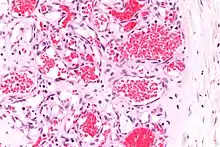

![]() | Capillary hemangioma | Micrograph showing capillary hemangioma of skin. | Category: Histopathology of capillary hemangioma | Capillary hemangioma |